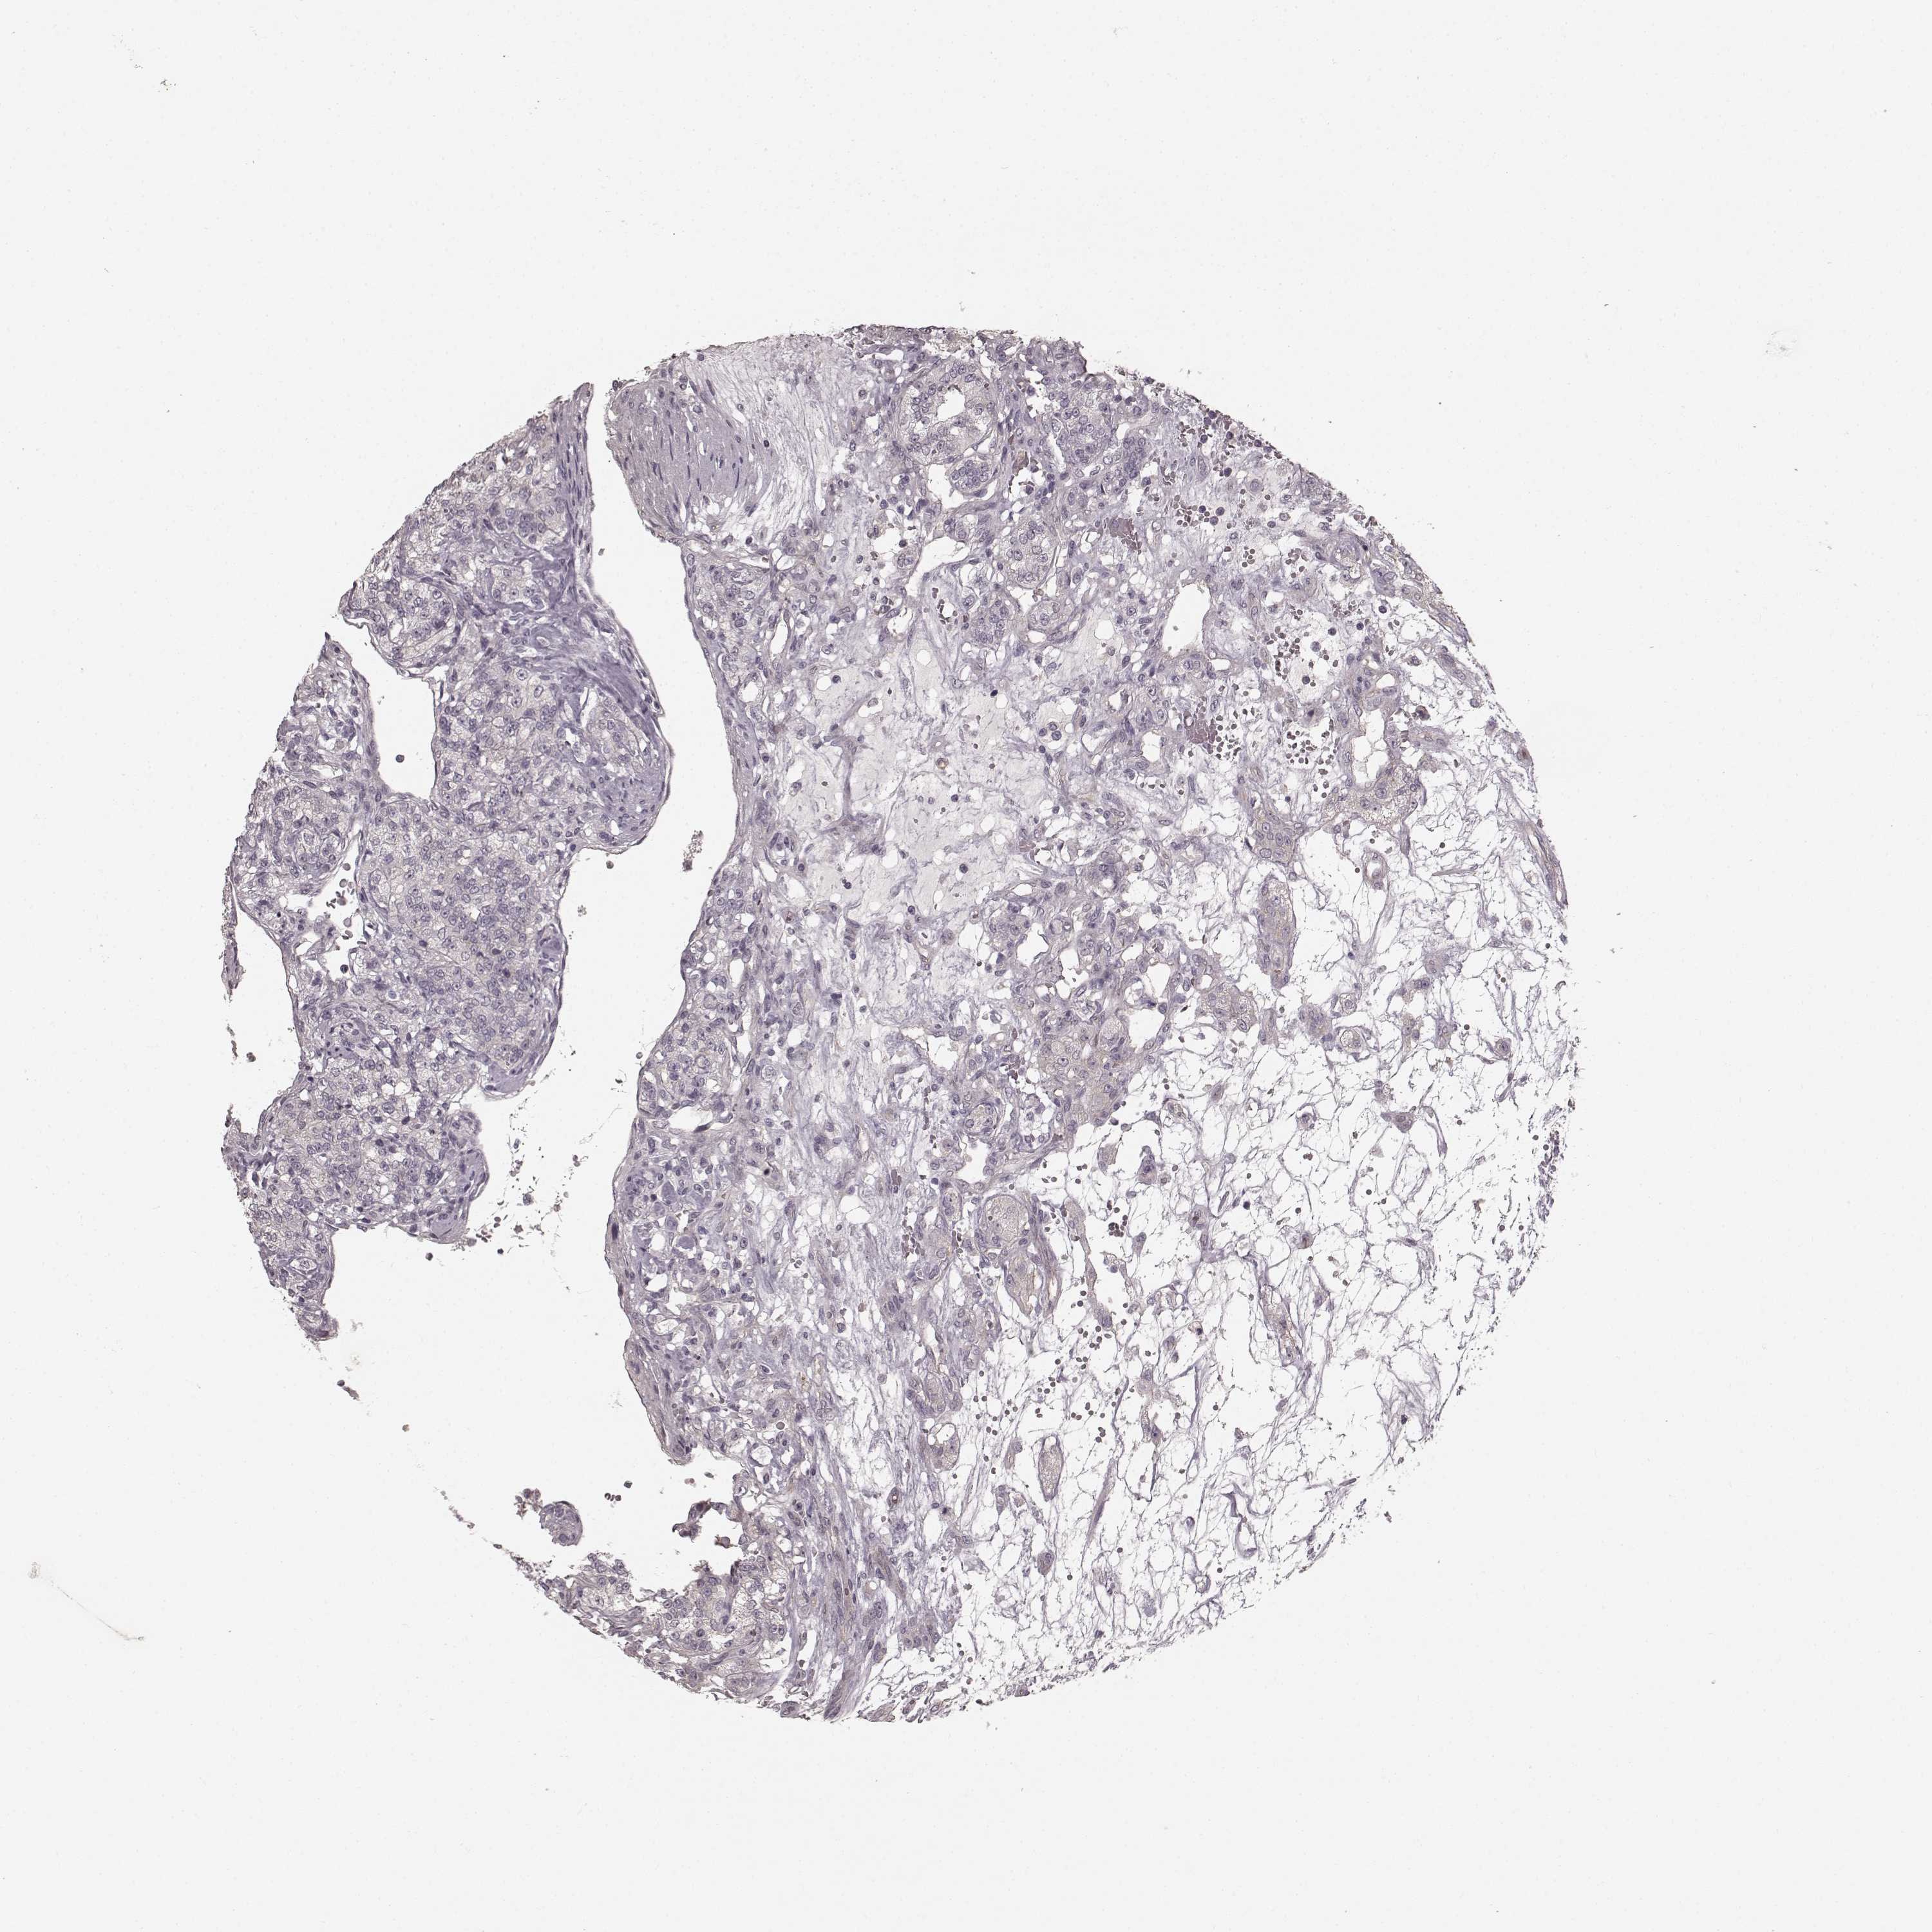

KIDNEY RENAL PAPILLARY CELL CARCINOMA (TCGA) - Interactive survival scatter ploti

The Survival Scatter plot shows the clinical status (i.e. dead or alive) for all individuals in the patient cohort, based on the same data that underlies the corresponding Kaplan-Meier plots. Patients that are alive at last time for follow-up are shown in blue and patients who have died during the study are shown in red.

The x-axis shows the expression levels (FPKM) of the investigated gene in the tumor tissue at the time of diagnosis. The y-axis shows the follow-up time after diagnosis (years). Both axes are complimented with kernel density curves demonstrating the data density over the axes. The top density plot shows the expression levels (FPKM) distribution among dead (red) and alive patients (blue). The right density plot shows the data density of the survived years of dead patients with high and low expression levels respectively, stratified using the cutoff indicated by the vertical dashed line through the Survival Scatter plot. This cutoff is automatically defined based on the FPKM cutoff that minimizes the p-score. The cutoff can be changed by dragging the vertical line or by entering a cutoff value in the square labeled "Current cut-off".

Under the Survival Scatter plot the p-score landscape (black curve; left axis) is shown together with dead median separation (red curve; right axis). Dead median separation is the difference in median mRNA expression between patients who have died with high and low expression, respectively. It is calculated as follows: median FPKM expression of dead patients with high expression - median FPKM expression of dead patients with low expression. This is intended to aid the user in visually exploring custom cutoffs and the associated p-scores and dead median separation.

Individual patient data is displayed and can be filtered by clicking on one or more of the category buttons on the top of the page. Categories describing expression level and patient information include: high, low, alive, dead, female, male and tumor stages. The scale of the x-axis can be toggled between linear and log-scale by clicking on the "x log" button. Mouse-over function shows TCGA ID, patient information and mRNA expression (FPKM) for each patient.

& Survival analysisi

Kaplan-Meier plots summarize results from analysis of correlation between mRNA expression level and patient survival. Patients were divided based on level of expression into one of the two groups "low" (under cut off) or "high" (over cut off). X-axis shows time for survival (years) and y-axis shows the probability of survival, where 1.0 corresponds to 100 percent.

PRKCE is not prognostic in Kidney Renal Papillary Cell Carcinoma (TCGA)

Best expression cut offi